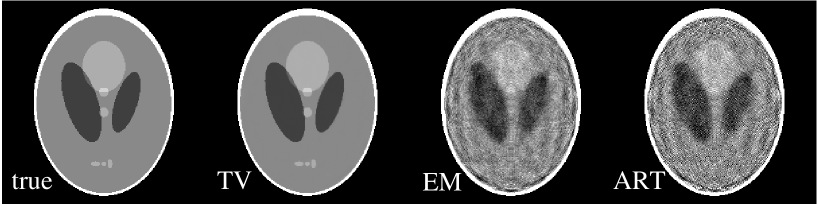

We demonstrate this point with the widely used Shepp-Logan phantom in Fig. 1. If the pixel values are labeled by , the image gradient magnitude is:

We refer to this quantity as the gradient image. The number of non-zero pixels in this 256x256 image is 32,668 , while the number of non-zero pixels in its gradient image is only 2,183.

III Numerical Results: ideal conditions

For the results in this section, we demonstrate and validate our TV algorithm under “ideal” conditions. The true image solution is taken to be the Shepp-Logan image shown in Fig. 1 discretized on a 256x256 pixel grid. This phantom is often used in evaluating tomographic reconstruction algorithms. As also shown in Fig. 1, its gradient image is sparse with only 2,183 non-zero pixels. This number is roughly only 6.7% of the 32,668 non-zero pixels of the Shepp-Logan image itself. Taking the result for Fourier inversion Candes et al. (2004) as a rule of thumb for the current problem, one might expect that a minimum of twice as many non-zero, independent projection measurements are needed for obtaining the image. Thus we suppose that a minimum of 4,366 measurements are required for the ERP. We first demonstrate the image recovery from sparse data with the few-view example shown below. Subsequently, we show the utility of the TV algorithm for other insufficient data problems where there are plenty of projection ray measurements, but the angular or projection coverage is less than the minimum for analytic reconstruction. The insufficient data problems demonstrated below are the limited scanning angle problem, and the “bad bins” problem where there is a gap on the detector for all available projection views.

The first case is a reconstruction problem from few-view projections in fan-beam CT. Using the Shepp-Logan phantom shown in Fig. 4A, we generated projection data at 20 view angles specified by:

| (19) |

Though sparse, the angles cover 360∘ about the object. The shift in the second half of the angular measurements helps to reduce redundancy in the scanned data. The total number of measurement rays is , but only 8,236 of these projection elements are non-zero. This number is larger than the twice the support of the gradient image, but it is well below the support of the Shepp-Logan phantom itself. In addition, the angular direction is severely undersampled.

From the projection data generated at the 20 views, we reconstructed images, as shown in row one of Fig. 4, by use of the TV, EM, and ART algorithms. The number of iterations for each algorithm was 200. For a quantitative comparison, we also compare the image profiles along the central lines of the images in the horizontal and vertical directions. The results in Fig. 4 indicate that the TV reconstruction is visually indistinguishable from the true image, suggesting that the system matrix corresponding to sparse fan-beam data may have the ERP even though the column vectors of the system matrix do not form an ortho-normal basis. The EM and ART results show considerable artifacts.